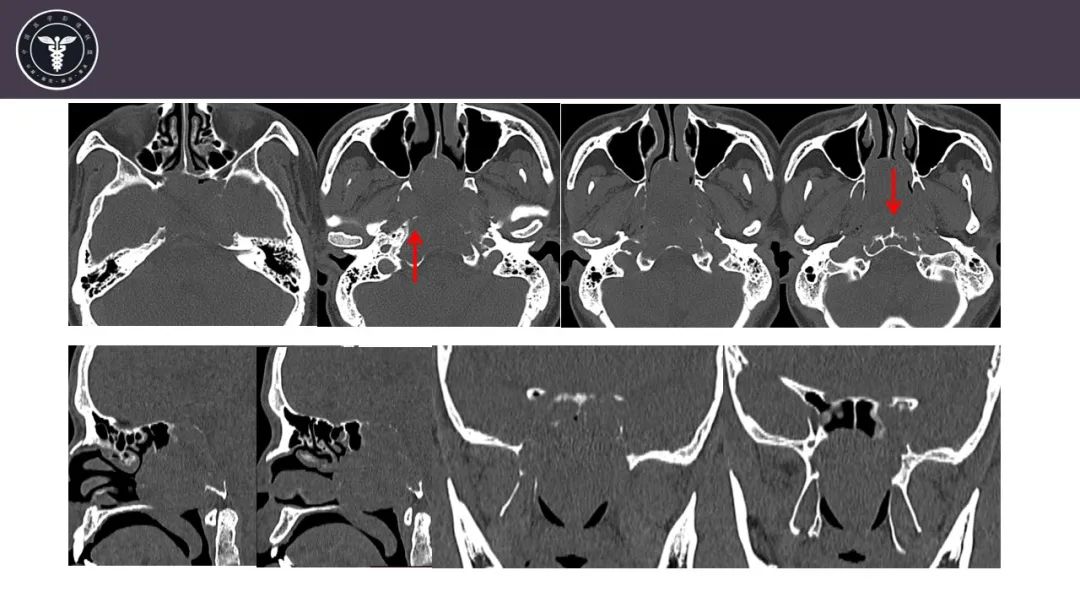

【病例】斜坡区骨巨细胞瘤 VS 脊索瘤-3

【病例】斜坡区骨巨细胞瘤 VS 脊索瘤-4